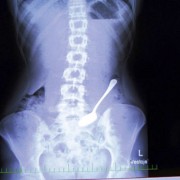

Батерии